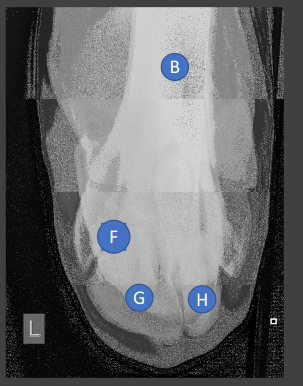

A

incomplete ossification in a young animal